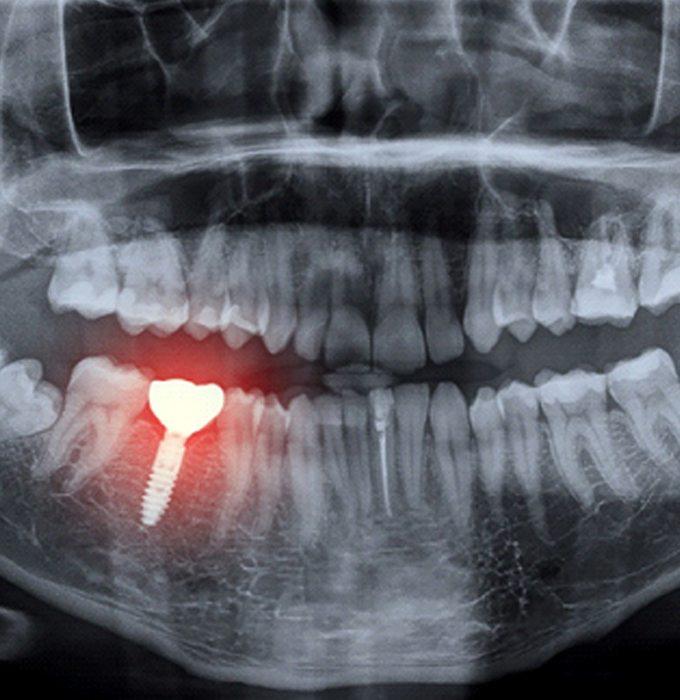

دندان‌پزشکی دیجیتال، آینده‌ی درمان‌های دهان و دندان است — ترکیبی از فناوری، دقت و زیبایی. در این روش، تمام مراحل از تشخیص تا طراحی لبخند، با ابزارهای دیجیتال و سه‌بعدی انجام می‌شود. اسکنرهای داخل دهانی، تصویربرداری سه‌بعدی، طراحی کامپیوتری و چاپ دیجیتال، جایگزین قالب‌گیری سنتی و مراحل طولانی درمان شده‌اند.

تحلیل دقیق توسط نرم‌افزار تخصصی

بررسی وضعیت فک، دندان و بافت‌های اطراف